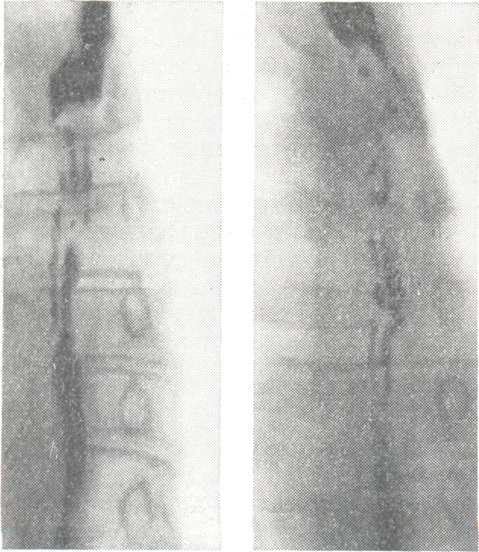

Синдром Баршоня — Тешендорфа: изменчивость рентгенологической картины пищевода (снимки сделаны с интервалом в 15 мин.).

Диагностика возможна лишь с помощью контрастного рентгенологического исследования, при к-ром определяется характерный четкообразный вид пищевода. Участки пищевода, расположенные между двумя соседними спастически сокращенными отрезками, могут иметь округлую, овоидную или неправильную косую форму. Нередко можно наблюдать спонтанное расправление спазмированных участков пищевода или перемещение их в каудальном направлении; в других случаях рентгеновская картина длительное время остается стабильной.

Применение атропина, папаверина, метацина, нитритов приводит к временному ослаблению или исчезновению спазмов и восстановлению проходимости пищевода. Изменчивость рентгенологической картины (рис.), а также реакция на указанные препараты позволяют правильно провести дифференциальную диагностику. В трудных для диагностики случаях может быть применена париетография пищевода (см. Париетография).